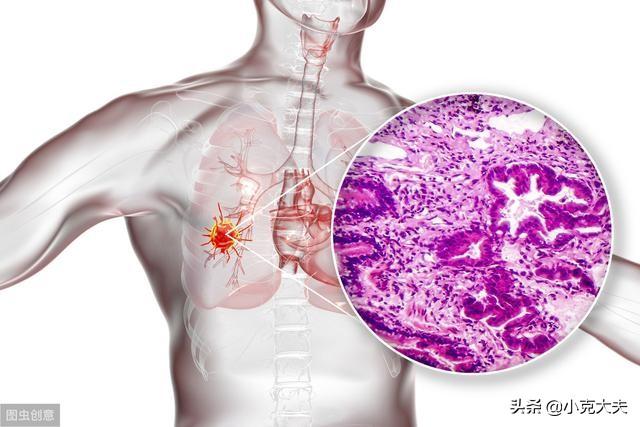

肺の重要性はいくら強調してもしすぎることはないが、肺がんはすべてのがんの中でトップであり、「ナンバーワンのがん」として知られている。

保健省の最新のがん統計によると、肺がんは現在、がんの中で第1位であり、「がんの王様」とも呼べる。 病気自体は(他のがんに比べて)深刻なものではないが、死亡率が高いのは、初期段階で症状を発見するのが難しいため、患者が中期や後期まで症状に気づかず、治療が難しくなるからである。死亡率が高いのは、初期段階で症状を発見するのが難しいため、患者が中期や後期まで症状に気づかず、治療が難しくなるからである。